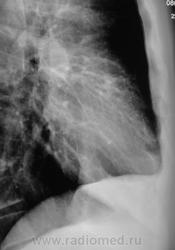

Боковая рентгенограмма.

Вот боковой!

Томограмм в этот раз не делали, а "клиника"? Так терапевт - лечащий свидетельствует, что клиника пневмонии есть.